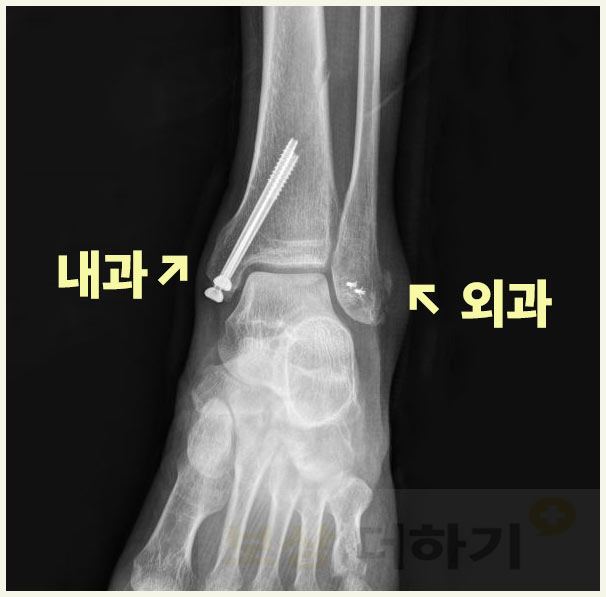

복사뼈는 발목의 복숭아뼈를 말하는데요. 주로 넘어지거나 발을 잘못 디뎌 부상이 생깁니다. 바깥쪽과 안쪽 복숭아뼈를 각각 외과(외복사), 내과(내복사)라고 하며 이중 한곳만 다치기도 하지만 심한 경우 두 곳이 모두 골절되기도 합니다.

실제 보상 사례 양쪽 복사뼈 골절 s82820

■ 사건 요약 사례자분은 출근길에 일어난 사고로 양측 복사뼈 모두 골절되는 부상을 입어 금속 핀으로 고정하는 수술을 하셨습니다. 다행히 출퇴근 재해로 산재 처리하여 치료비, 휴업급여, 장해급여가 지급되었습니다. 이후에는 개인보험 청구도 했는데요. 실비를 청구하여 비급여 치료비 일부와 골절 진단비, 수술비 등도 받으셨습니다. ■ 후유장해 기준 검토 이 외 가장 중요한 것이 바로 장애에 대한 보상이죠. 오 ** 님은 양쪽 복숭아뼈를 모두 다쳐 발목 운동 범위가 상당히 제한된 상태였습니다. 이에 해당되는 약관의 장애 기준을 다음 표로 간단히 살펴볼 수 있습니다.